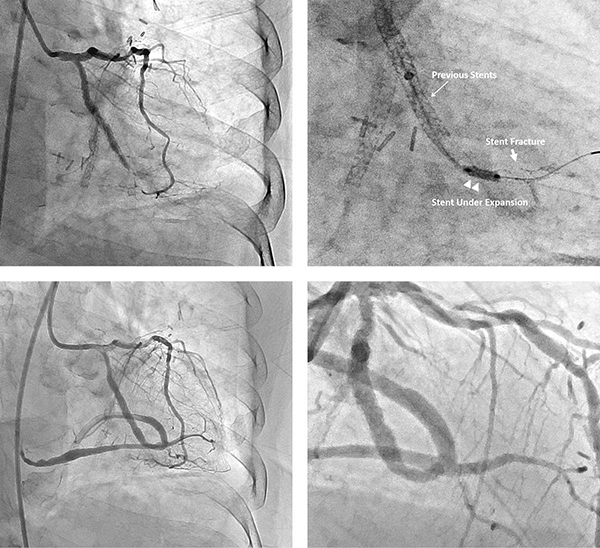

Пацієнту успішно виконано коронарну інтервенцію з використанням стандартних методів під контролем Hi-Def детектору. Оклюзію в стенті перетинали за допомогою мікрокатетера та гідрофільного провідника 0,014. Після успішної балонної ангіопластики з балоном діаметром 2 мм із використанням стандартного збільшення, для вивчення архітектури стента було використано зображення з високою роздільною здатністю. Зображення високої чіткості (Hi-def) з 3-дюймовим полем зору дозволило чітко розрізнити окремі структури стенту та визначити його дефект (розрив), який не було видно у стандартному режимі.

Ангіопластика була застосована для розширення встаноленого раніше стенту, а новий стент (діаметром 2,5 мм із тонкими краями) було встановлено у гілці тупого краю. Під час ЧШВ DTS використовувався для мінімізації опромінення. Незважаючи на тривалість опромінення та процедури 35 та 119 хвилин, було кількісно визначено пікову шкірну дозу лише 1,0 Гр, ймовірно, через використання меншого кута огляду над зоною лікування в режимі Hi-Def. Пацієнт одужав без ускладнень, стенокардії під час спостереження не було.

Оклюзія артерії тупого краю (раніше встановленого стенту), зображеного у 3" Hi-Def режимі (верхнє праве зображення) порівняно з 8" FOV (верхнє ліве зображення) під час процедури ЧШВ. Пацієнт пройшов успішну ангіопластику, як показано на 3" Hi-Def зображенні (внизу праворуч), 8" FOV зображення під різними кутами зроблено для порівняння(внизу ліворуч).